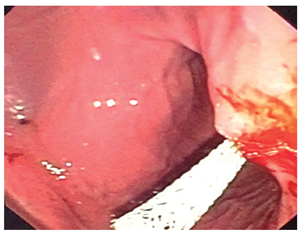

Se retiró el balón de dilatación y se insertó una prótesis biliar metálica autoexpandible completamente cubierta de 10 mm x 80 mm cuya copa distal quedó en el pseudoquiste pancreático, el cuerpo de la prótesis en la pared gástrica y la copa proximal en la luz del estómago (Figura 2).

Se drenaron 100 mL de material seropurulento, sin sangrado de la pared, sin neumoperitoneo y sin ninguna otra complicación.

Se realizó un control endoscópico al cuarto día después del procedimiento con un posicionamiento adecuado del stent en funcionamiento. En la evolución posterior al procedimiento desapareció el dolor y la fiebre, toleró la vía oral y disminuyeron los parámetros inflamatorios (Figura 3).